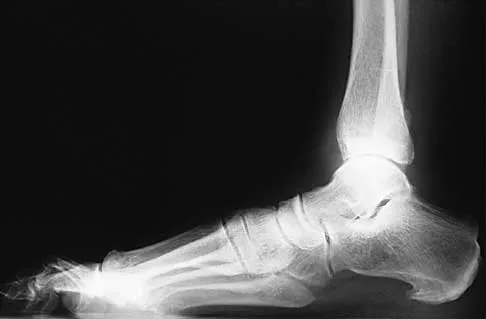

A 25-year-old student sustains the injury shown in Figures 13a through 13c after falling off a curb. Initial management should consist of

Explanation

The radiographs reveal a fracture entering the 4-5 intermetatarsal articulation, consistent with a zone 2 injury. This classically is also referred to as a Jones fracture. The history and radiographic findings indicate this is an acute fracture, which guides management. A zone 1 fracture enters the fifth tarsometatarsal joint, and a zone 3 fracture is a proximal diaphyseal fracture distal to the 4-5 articulation. Initial management is usually nonsurgical and consists of non-weight-bearing in a short leg cast. This method has been shown to result in a better healing rate compared to weight bearing as tolerated. Rosenberg GA, Sterra JJ: Treatment strategies for acute fractures and nonunions of the proximal fifth metatarsal. J Am Acad Orthop Surg 2000;8:332-338.